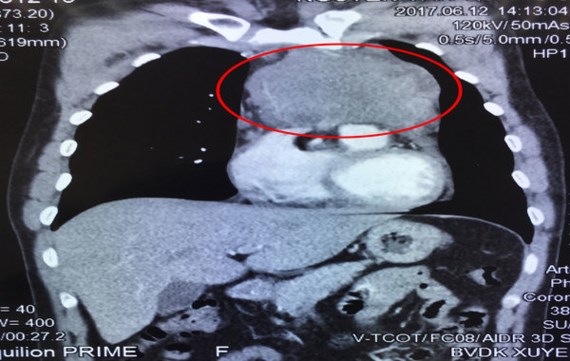

Ảnh chụp CT khối u (khoanh đỏ) trong lồng ngực bệnh nhân trước phẫu thuật.

Sau khi thăm khám kỹ lưỡng, thực hiện chụp cắt lớp vi tính 160 lát (CT) cùng các thăm dò cận lâm sàng cần thiết khác, các bác sĩ xác định có 1 khối u xuất phát từ trung thất trước, xâm lấn rộng vào màng ngoài tim, tĩnh mạch vô danh, thần kinh hoành bên trái, động mạch phổi và lan ra sau dính vào động mạch chủ ngực xuống.